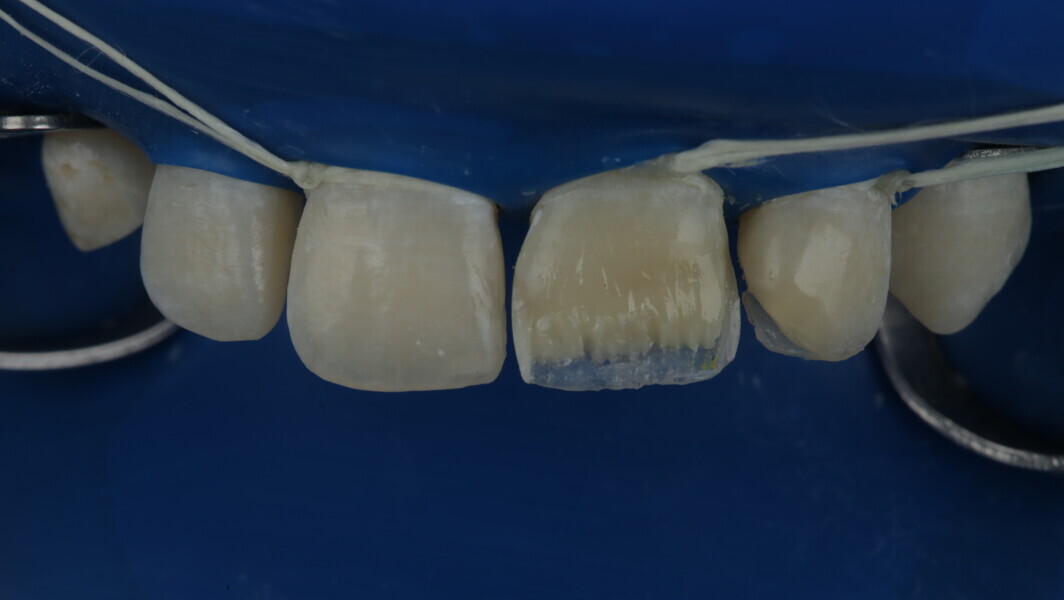

Fig 8-18: Bonding and palatal shell

Fig 19-24: Contact build-up with band and wedge

Fig 25-30: Layering protocol step by step